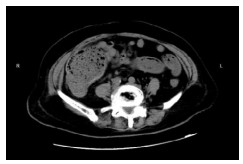

1 资料与方法病例1,患者女,72岁,2020年9月2日因“腹痛3 d”来本院急诊,拟“升结肠肿瘤伴肠梗阻”收住院。半月前因“胆囊结石”在当地医院行腹腔镜下胆囊切除术。本次入院查体:腹部膨隆,右下腹部压痛明显,轻度反跳痛。WBC13.3×109/L, N 84.0%。腹部增强CT提示升结肠管壁不规则增厚伴管腔狭窄,回盲部及远端回肠扩张明显(图 1)。肠镜检查:升结肠肿物,予取病理活检后,在肠道狭窄处行肠梗阻金属支架植入解除梗阻(以维持肠腔的通畅性和减少肠道毒素的进一步吸收)。肠镜病理提示:(升结肠)管状绒毛状腺瘤,部分高级别上皮内瘤变。3 d后复查腹部平扫CT示回盲部及远端回肠原先扩张的肠腔已明显缩小(图 2)。因患者既往有糖尿病史,时常合并胸闷胸痛,心电图示侧壁T波直立,心内科会诊建议行心脏冠脉造影。冠脉造影提示心脏左前降支中段狭窄约百分之八十,远端约百分之九十狭窄。经多学科讨论后认为患者目前急性肠梗阻症状已经缓解,建议可先予冠状动脉药物涂层支架植入术,再予以替格瑞洛口服抗凝治疗,1个月后再次入院行结肠肿瘤手术。患者于2020年10月9日再次入院行腹腔镜下右半结肠癌根治手术,手术过程顺利。术后病理报告:(升结肠)高-中分化腺癌,T3N1M0。患者术后13 d出院,并接受了后续的规律化疗。目前患者恢复良好。

| 图 1 腹部增强CT示回盲部及远端回肠扩张明显、肠腔充满肠道内容物 |